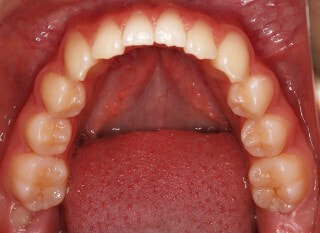

治療前